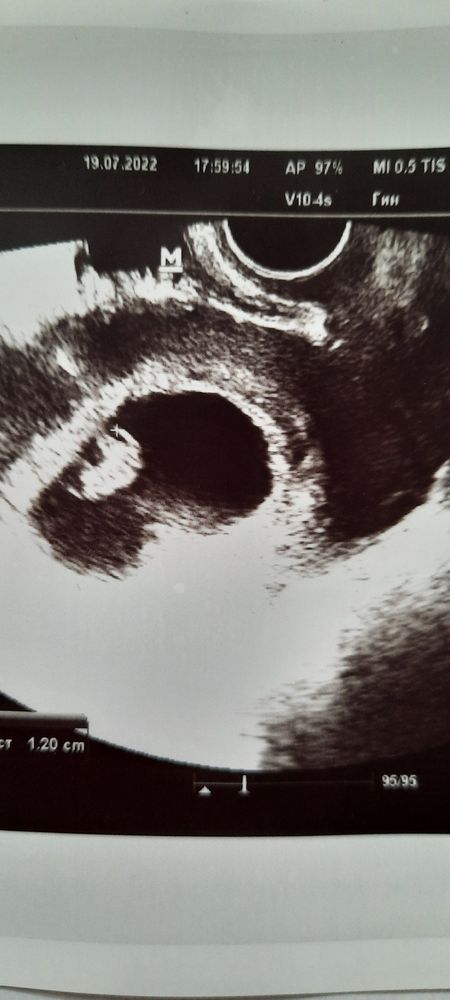

Добрый день,милые беременюшки!Ну вот я снова с вами, хотя уже думала,что на третьем сынуле остановлюсь....но вот судьба решила иначе.Первый раз без приёма гормонов,без подготовки к беременности,Бог наградил нас ещё одной пуговкой)))Помогите,пожалуйста, определить кого на этот раз ждём, мальчика или девочку по методу Рамзи?Узи на 7-8 недели беременности, трансвагинально